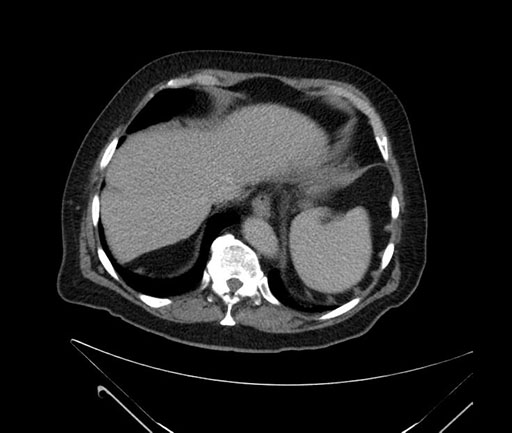

Imaging Analysis

Look through the patient's CT scan to identify any areas of concern for the necessary procedure.

Based on your CT findings, which issue(s) would give reason for "planned slowing down moment(s)" in this case?